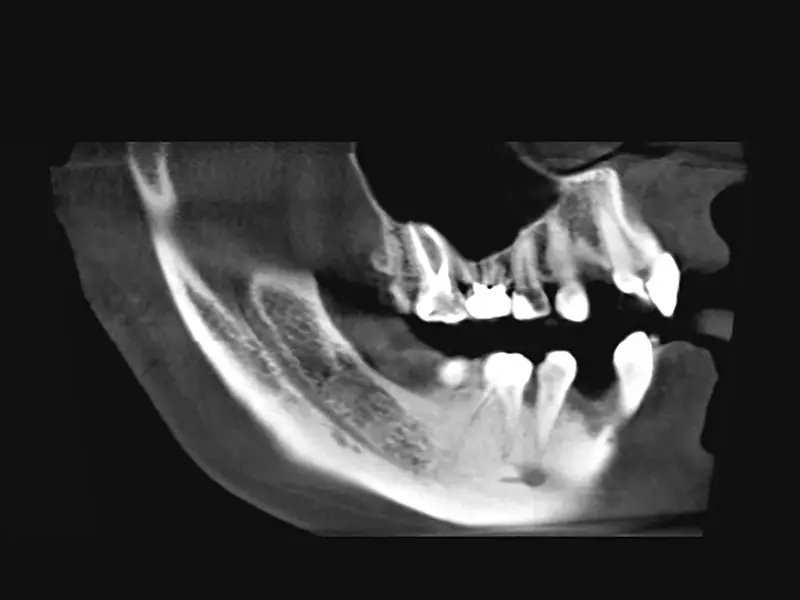

Ząb 48. całkowicie wyrżnięty, zakwalifikowany do ekstrakcji z powodu zgłaszanych przez pacjentkę dolegliwości bólowych i braku zgody na leczenie endodontyczne (zdj. 11). Na zdjęciu rentgenowskim ząb ułożony prawidłowo, pionowo, skierowany lekko w kierunku języka. Korzeń mezjalny mocno wygięty dystalnie (zdj. 12).

Ząb 38. częściowo zatrzymany, z widocznym guzkiem policzkowym mezjalnym przebitym przez błonę śluzową (zdj. 17). Na zdjęciu pantomograficznym ząb o niewielkim stopniu inklinacji mezjalnokątowej, jednokorzeniowy (zdj. 18).

Pacjent zgłosił się w celu usunięcia zęba 38. W badaniu klinicznym stwierdzono ząb w pełni pokryty błoną śluzową (zdj. 24). Na zdjęciu rentgenowskim ząb częściowo zatrzymany, o ułożeniu mezjalnokątowym, dwukorzeniowy, z niewielkim przejaśnieniem wokół korony zęba (zdj. 25).